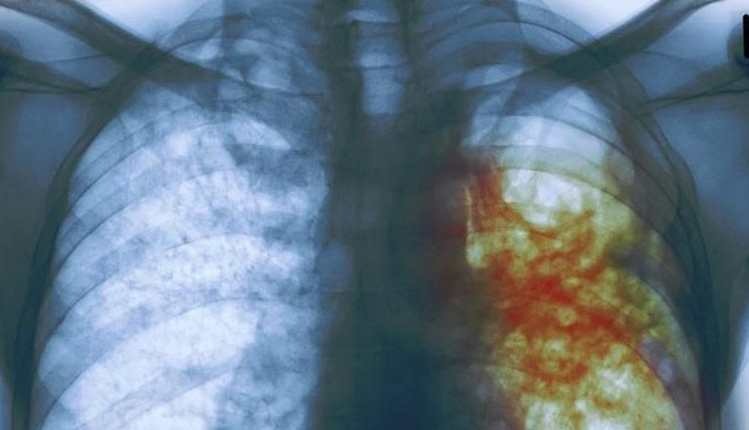

Día Mundial de la Tuberculosis: 10 datos que debe conocer sobre esta enfermedad

Qué es la tuberculosis latente que afecta a una de cada 4 personas

Según la OMS, el coronavirus pone en peligro los logros en la lucha contra la tuberculosis

The Lancet: impacto de COVID-19 puede elevar muertes por VIH, tuberculosis y malaria